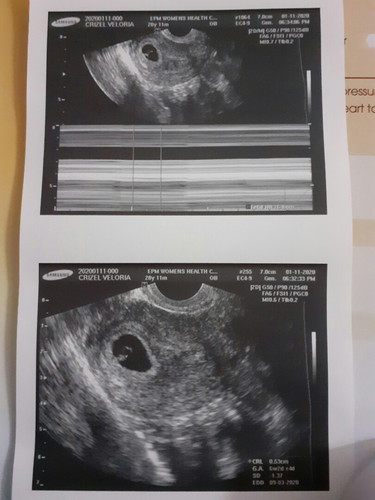

Good pm po, ask ko lang po kung naresetahan po ba kayo ng duphaston twice a day. Dahil daw nasa may bandang gitna si baby wala pa siya dun sa bandang taas. Dati kasi sa unang check up ko dahil sa palaging sumasakit ang puson at balakang ko niresetehan niya nko ng duphaston 3 times a day, ngayon twice a day na lang. Normal lang po kaya yun? Salamat po sa mag cocomment po :) God bless